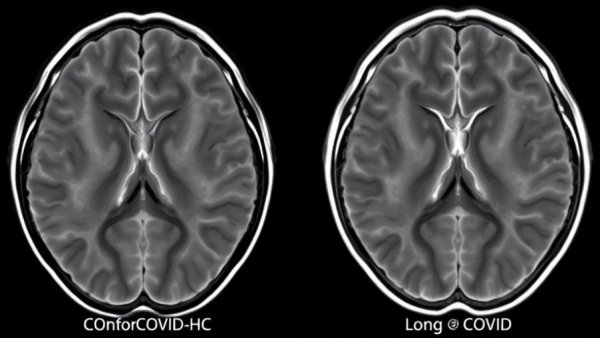

The COVID-19 pandemic has had significant ramifications beyond the respiratory symptoms for which it is predominantly known. Recent research conducted at Griffith University reveals that, even among those who have "fully recovered" from the virus, there may be lingering effects on the brain that emerge months or even years after infection. This finding is underscored by advanced MRI techniques that showcased alterations in brain structure and chemistry, pointing to potential long-lasting neurological consequences of the virus.

As Dr. Kiran Thapaliya, lead author of the study, notes, the research aimed to compare the brain health of individuals who had recovered from COVID-19 with those who had never contracted the virus. The results yielded notable divergences indicating that even in the absence of acute symptoms, the brain may retain scars from the infection. These structural changes were observed across various brain regions critical for memory, cognition, and overall brain health.